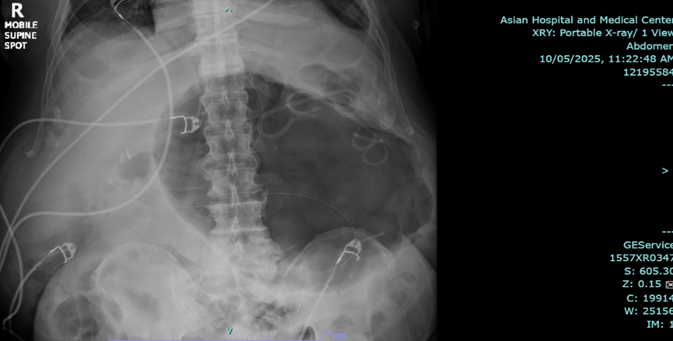

Endoscopic esophagogastroduodenoscopy plus endoscopic internal drainage using plastic stent and insertion of duodenal tube were done on 23 September 2025, repositioned to the jejunum on 29 September 2025. By x-ray (5 October 2025), a gas-filled mass is still appreciated in the upper abdomen, in the region of the stomach. The feeding tube was seen coursing within, with its tip located lateral to the mass, which may be in the distal segment of the stomach. No distinct kink was noted in this study.

The patient was readmitted for fever and anemia, and resolved accordingly. X-ray of abdomen showed unchanged gas-filled focus.

Figure 3a,b: X-ray of abdomen.